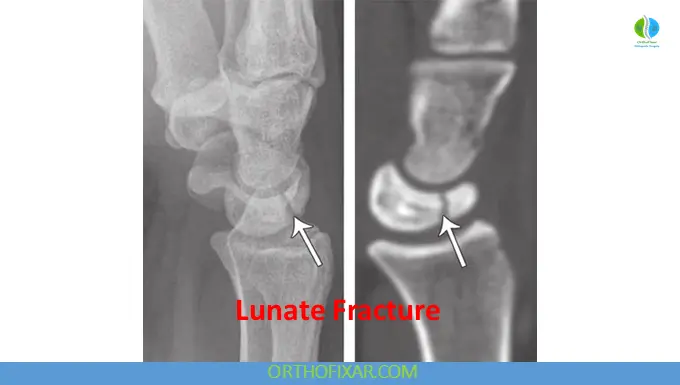

Imaging and Diagnosis

Standard radiographic evaluation includes posteroanterior (PA) and lateral wrist views. However, these are frequently insufficient due to overlapping carpal structures obscuring the lunate.

Advanced imaging plays a crucial role:

- Oblique radiographs may improve visualization

- CT scans provide superior detail and are considered the gold standard for detecting fractures

- MRI is essential for assessing vascular integrity and is particularly valuable when evaluating for osteonecrosis or Kienböck disease